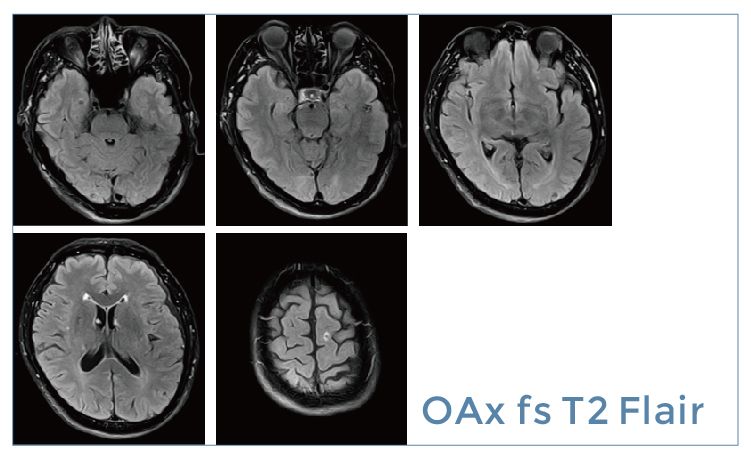

【朗润影像档案】20190524磁共振影像病例结果讨论